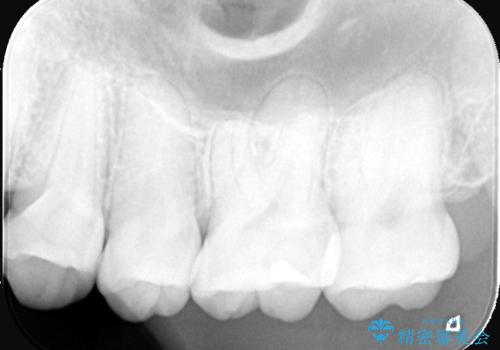

2回で完了した奥歯のセラミック修復

- 奥歯の虫歯治療を主訴にご来院されました。患者様から「できるだけ通院回数を少なく、早く治療を終わらせたい」というご要望があったため、短期間での完了を目指し、セラミックインレー(詰め物)とセラミッククラウン(被せ物)を併用する治療計画を立案しました。治療は精密機器を活用し、2回の来院で最終的なセラミック修復物を装着することを目指します。

今回の治療では、虫歯の大きさや深さに応じて、異なるセラミック修復法を適用しました。

比較的軽度な虫歯には、セラミックインレー(詰め物)で対応し、健全な歯質を最大限に残しました。

進行した虫歯や歯の強度が低下している歯には、セラミッククラウン(被せ物)を選択し、歯全体を保護することで破折を防ぎました。

短期間での治療を可能にしつつ、天然歯と見分けがつかない審美性と、長期的に安定する機能性を兼ね備えたセラミック修復を実現しました。